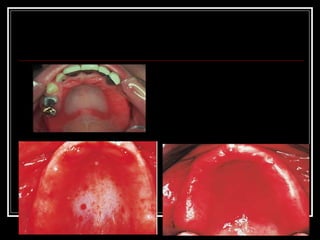

Denture Induced Stomatitis, also known as denture sore mouth, is a common condition affecting up to 70% of denture wearers, characterized by erythema and swelling of the palate mucosa in contact with the dentures. It is caused mainly by Candida albicans accumulating on dentures due to poor oral and denture hygiene. Treatment involves improving hygiene, removing dental plaque from dentures and mucosa, and using antifungal medications like nystatin drops or miconazole gel.